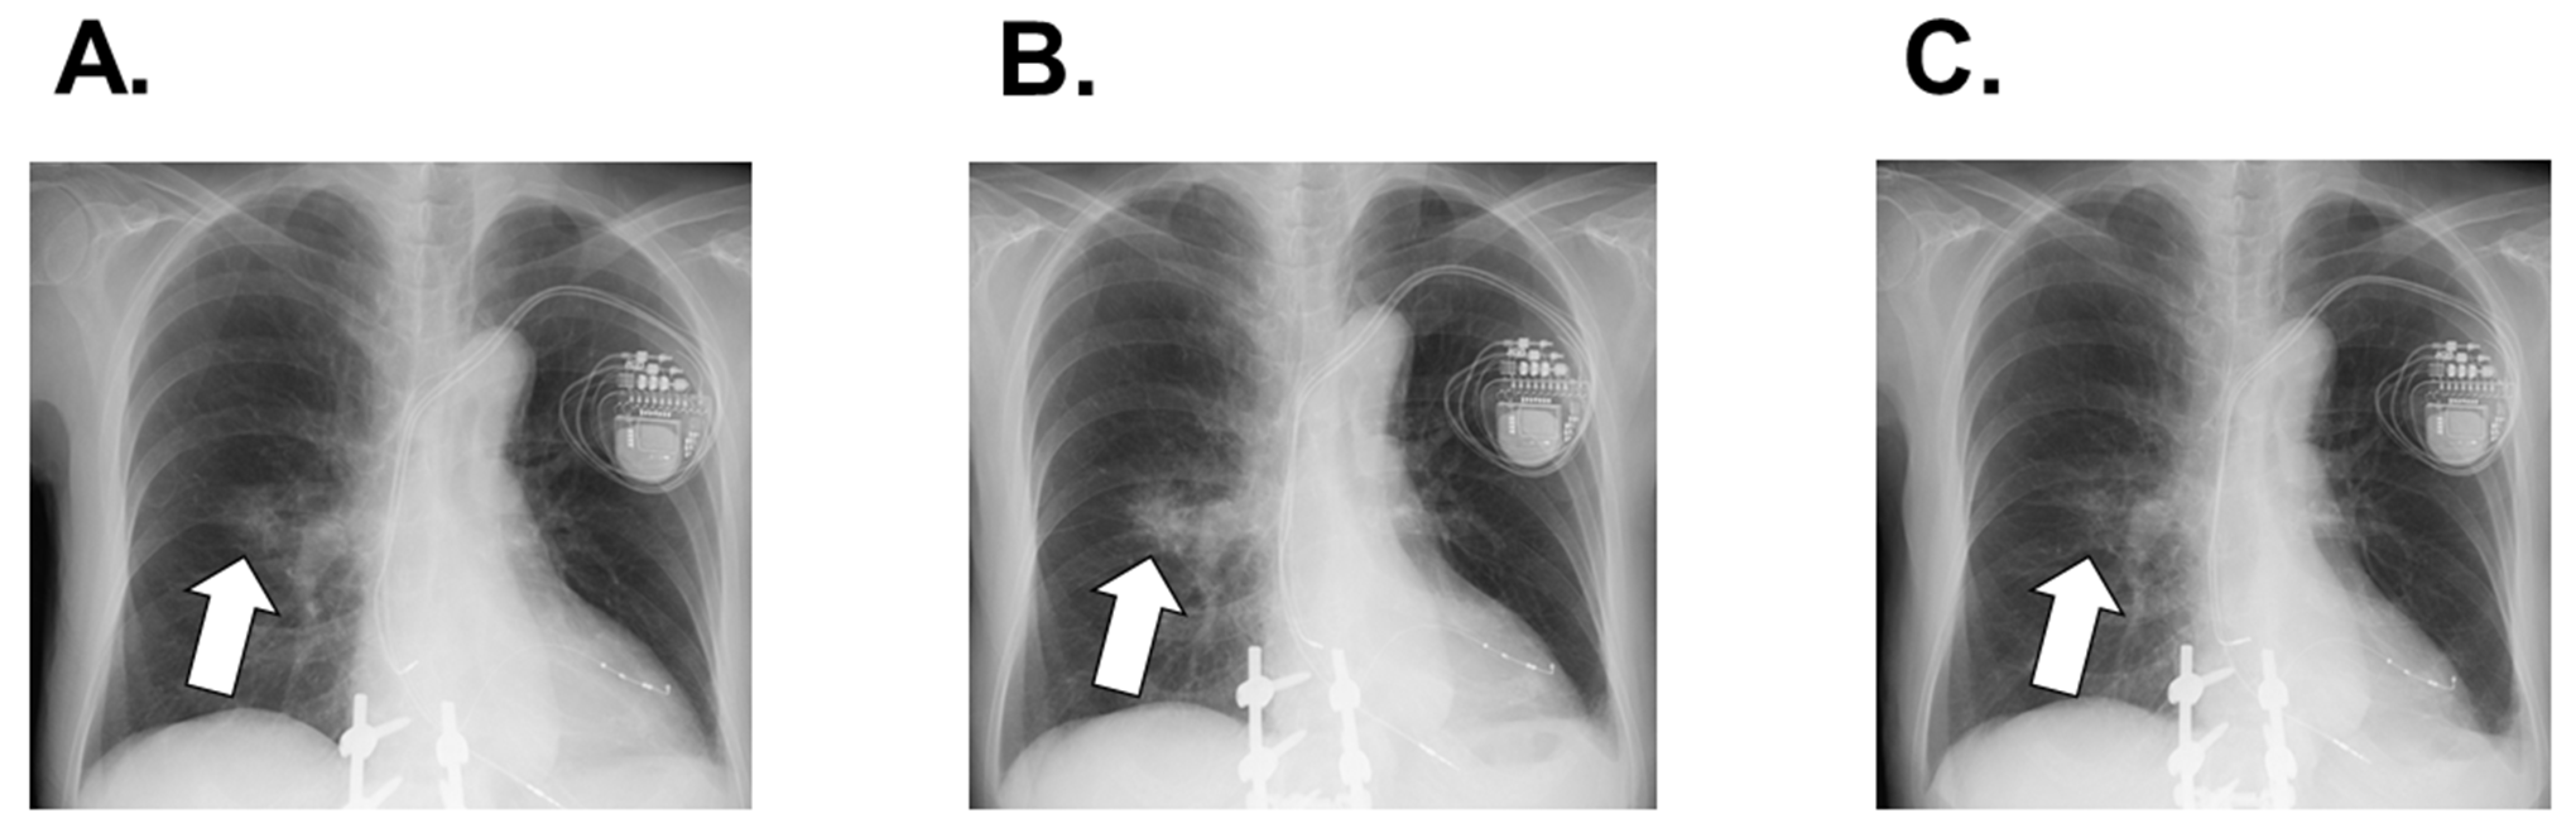

2.2. On Admission

2.3. In-Hospital Course

2.4. Post-Discharge Course